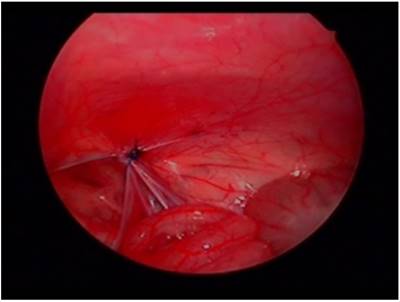

Patients underwent surgery with pelvis slightly elevated in supine position. A 5 mm, 30° angled laparoscope was inserted above or through the umbilicus. We maintained an 8mmHg pressure for pneumoperitoneum, confirmed unilateral hernia, and evaluated contralateral side processus vaginalis opening. Two 2.7 mm laparoscopic needle holders were inserted into both abdominal sides at the level of umbilicus. The internal opening of inguinal hernia was then ligated using a purse string suture method. In the case of the opposite-side PPV, it was sutured using the same method (Fig. 1, Fig. 2). Contralateral PPV repair indication was: depth of PPV > 1 cm, no relation with diameter of PPV or shape.

Fig 1

Laparoscopic view of hernia site.